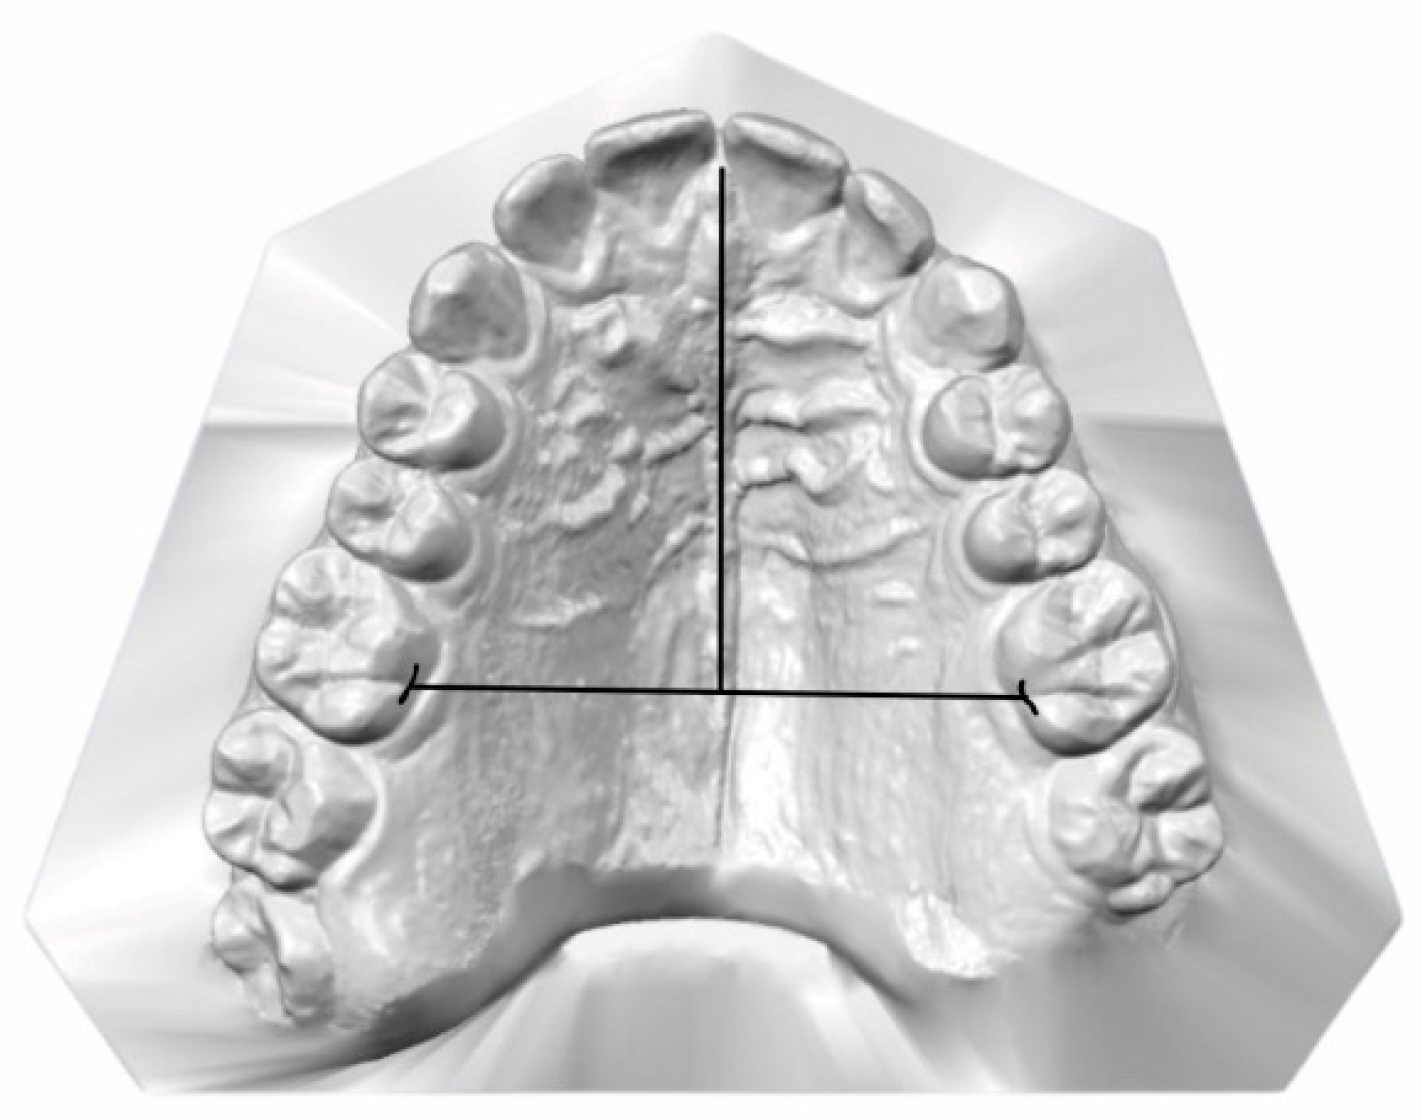

2.3. Data Collection and Measurements